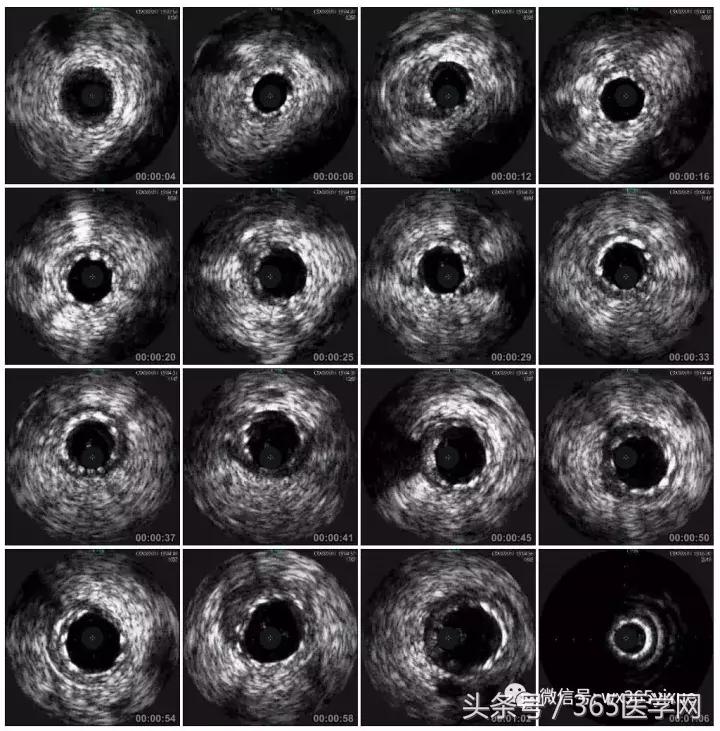

RCA闭塞段球囊扩张后IVUS

支架术后IVUS

明确IVUS在CTO介入的重要性,